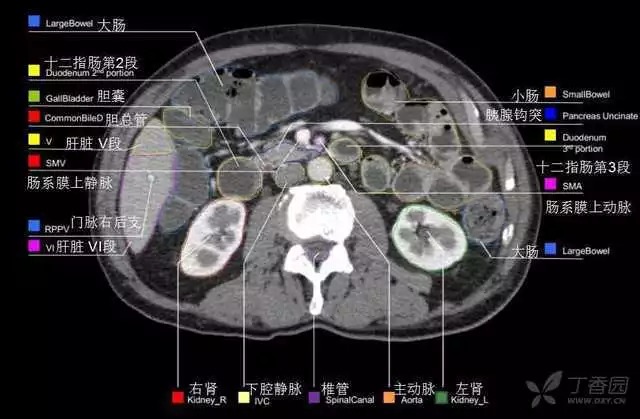

腹部肝脏高清CT断层的图谱

全腹部高清CT图谱,淋巴结彩色图谱,血管解剖图谱大汇总!

超声肝脏分叶及分段

肝脏分段和基本解剖学标志